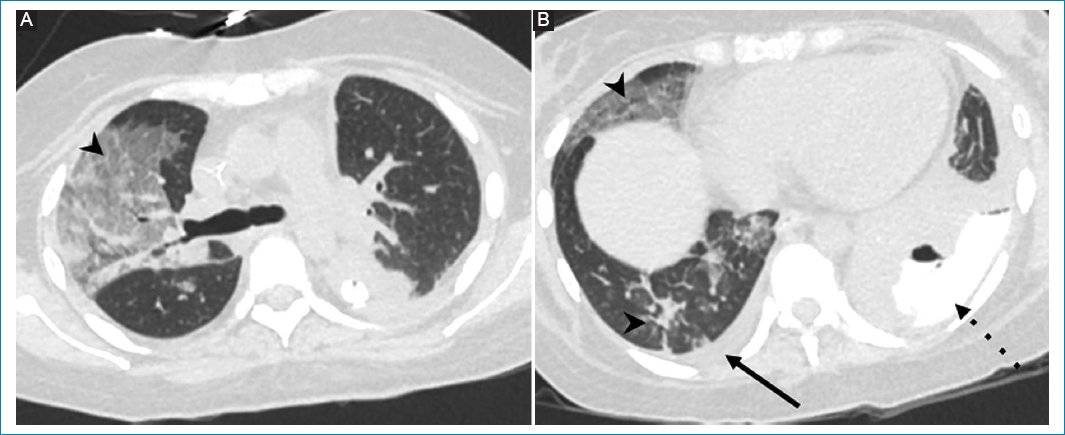

Figura 2. (A y B) Cortes axiales de TC de tórax que muestran múltiples áreas de aumento de la atenuación en vidrio esmerilado con sectores consolidativos en el pulmón derecho, vinculable a un proceso inflamatorio-infeccioso (puntas de flecha). Además, se observa derrame pleural derecho laminar (flecha). En la cavidad pleural izquierda se observa el contraste oral proveniente de la luz digestiva (flecha punteada).